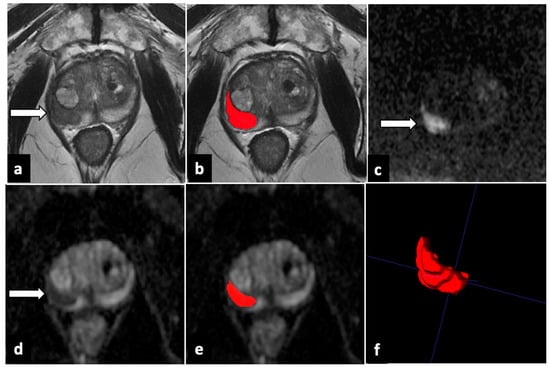

2.4. Image Analysis and Lesion Segmentation